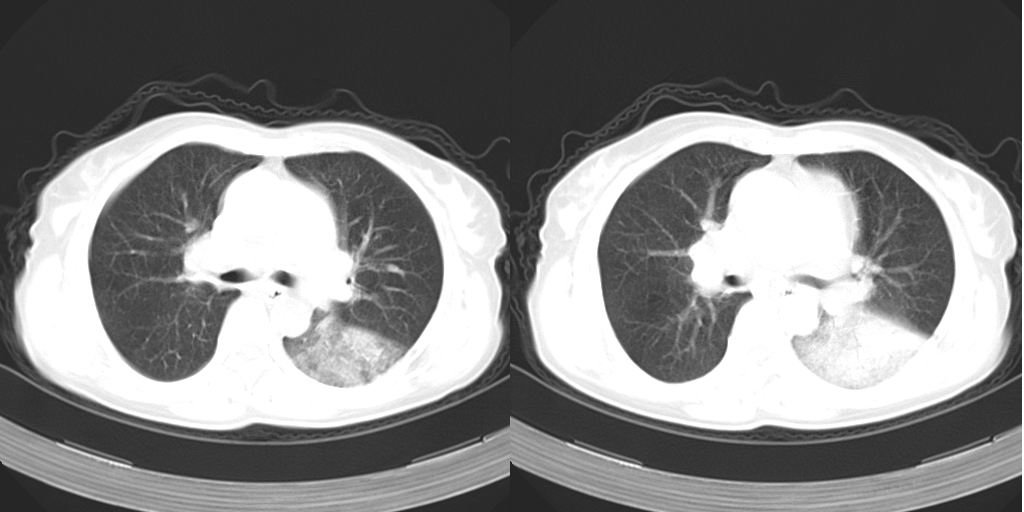

以下是引用dyqct在2007-1-23 15:01:00的发言:[br]左肺下叶实变、略萎陷,近肺门下部密度不均。上腔静脉后及隆突前见肿大淋巴结。余未见异常。[br]考虑:1、左肺下叶中心型肺癌伴肺不张、纵隔淋巴结转移;[br] 2、建议增强扫描并做任意平面重建确定肿块范围及支气管受累情况。

以下是引用dyqct在2007-1-23 15:01:00的发言:[br]左肺下叶实变、略萎陷,近肺门下部密度不均。上腔静脉后及隆突前淋巴结太多了,左下叶气管边窄、截断。余未见异常。[br]考虑:1、左肺下叶中心型肺癌伴肺不张、纵隔淋巴结转移;[br] 2、建议增强扫描并做任意平面重建确定肿块范围及支气管受累情况。

以下是引用同在2007-1-23 19:59:00的发言:[br]左肺下叶中央型肺癌伴肺不张及纵隔淋巴结转移.